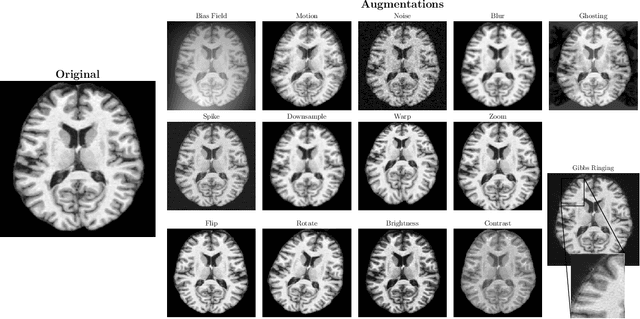

Abstract:Voxel-based Morphometry (VBM) has emerged as a powerful approach in neuroimaging research, utilized in over 7,000 studies since the year 2000. Using Magnetic Resonance Imaging (MRI) data, VBM assesses variations in the local density of brain tissue and examines its associations with biological and psychometric variables. Here, we present deepmriprep, a neural network-based pipeline that performs all necessary preprocessing steps for VBM analysis of T1-weighted MR images using deep neural networks. Utilizing the Graphics Processing Unit (GPU), deepmriprep is 37 times faster than CAT12, the leading VBM preprocessing toolbox. The proposed method matches CAT12 in accuracy for tissue segmentation and image registration across more than 100 datasets and shows strong correlations in VBM results. Tissue segmentation maps from deepmriprep have over 95% agreement with ground truth maps, and its non-linear registration, using supervised SYMNet, predicts smooth deformation fields comparable to CAT12. The high processing speed of deepmriprep enables rapid preprocessing of extensive datasets and thereby fosters the application of VBM analysis to large-scale neuroimaging studies and opens the door to real-time applications. Finally, deepmripreps straightforward, modular design enables researchers to easily understand, reuse, and advance the underlying methods, fostering further advancements in neuroimaging research. deepmriprep can be conveniently installed as a Python package and is publicly accessible at https://github.com/wwu-mmll/deepmriprep.